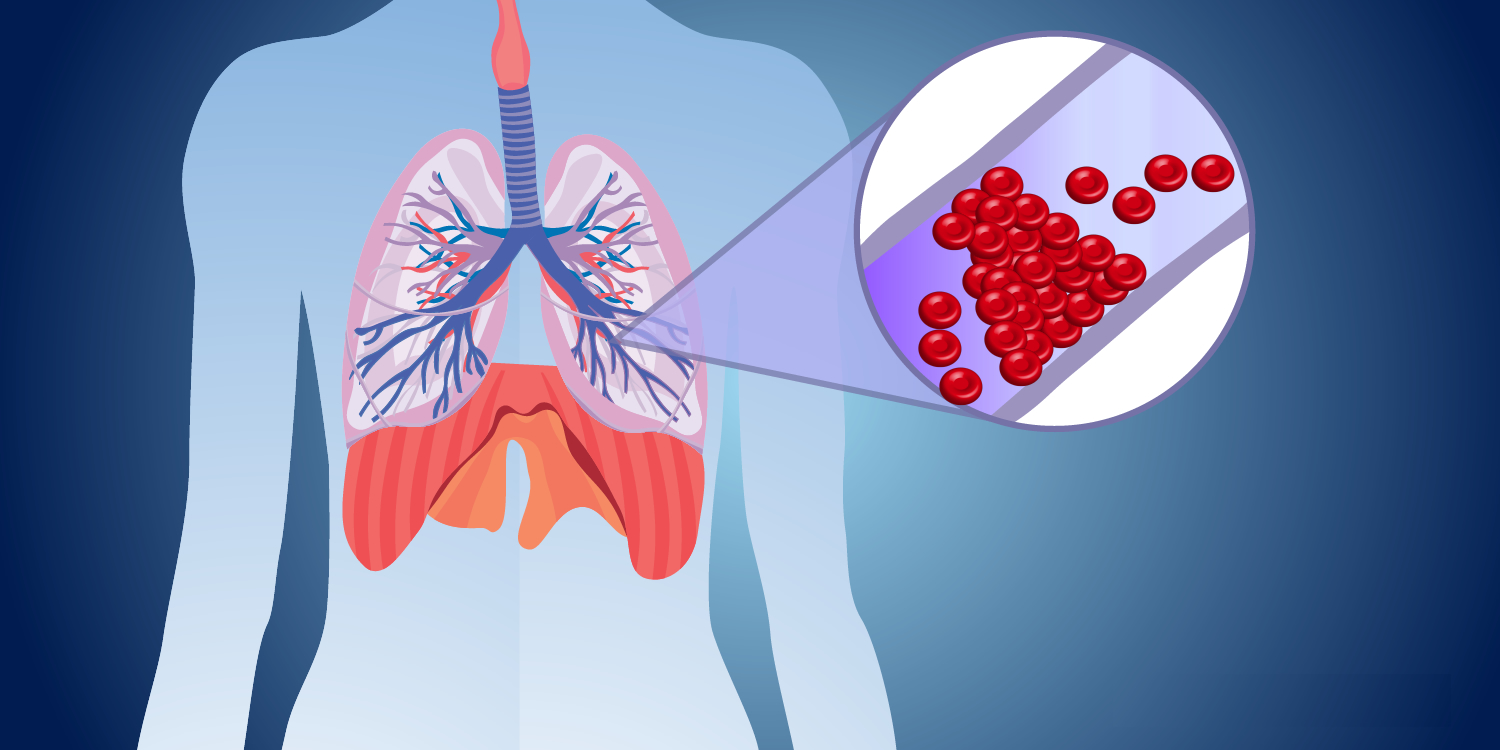

Η πνευμονική εμβολή είναι μια σοβαρή ιατρική πάθηση που συμβαίνει όταν ένας θρόμβος αίματος φράσσει μια αρτηρία στους πνεύμονες.

Ένας θρόμβος αίματος μπορεί να ξεκινήσει συνήθως από τα πόδια ή τις φλέβες στην λεκάνη (εν τω βάθει φλεβική θρόμβωση). Σε κάποιο σημείο, εάν δεν αντιμετωπιστεί, αυτός ο θρόμβος μπορεί να φτάσει στους πνεύμονες. Εκεί, εγκαθίσταται στις πνευμονικές αρτηρίες και αρχίζει να εμποδίζει τη φυσιολογική ροή του αίματος στους πνεύμονες.

Σε σπάνιες περιπτώσεις, η αρτηρία μπορεί να αποκλειστεί από κάτι άλλο εκτός από θρόμβο αίματος, όπως μια φυσαλίδα αέρα ή μέρος ενός όγκου. Είτε έτσι είτε αλλιώς, η απόφραξη προκαλεί βλάβη στον πνεύμονα και μειώνει την ποσότητα του οξυγόνου στο αίμα που ταξιδεύει προς τα έξω για να θρέψει το σώμα. Σε ορισμένες περιπτώσεις, όταν η απόφραξη υποχρεώνει την καρδιά να εργαστεί πολύ πιο έντονα, αυξάνεται η αρτηριακή πίεση στους πνεύμονες κι έτσι η πνευμονική εμβολή μπορεί να οδηγήσει σε πνευμονική υπέρταση.